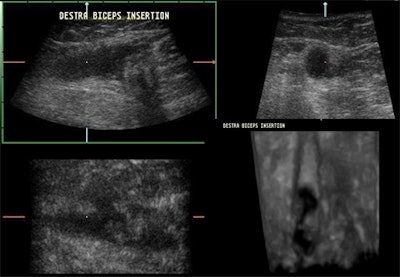

![]() |

| A lengthways split results in two cords, giving the appearance of two tendons lying side by side over a variable length of the tendon, as may be seen in the multiplanar images above. |